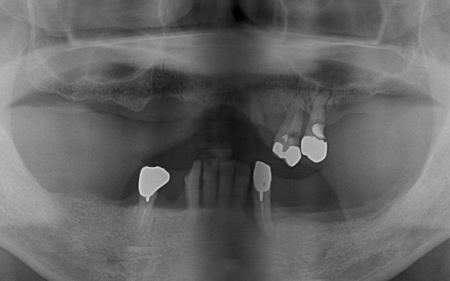

拝見したところ、上下の顎には入れ歯が装着されていましたが、破損して使えなくなっていました。

まず、上顎の状態や残存歯について詳しく検査し、温存が難しいと判断した左上の歯3本(犬歯、第1小臼歯、第2小臼歯)を抜きました。

抜歯後は、即時インプラント埋入手術を実施しています。